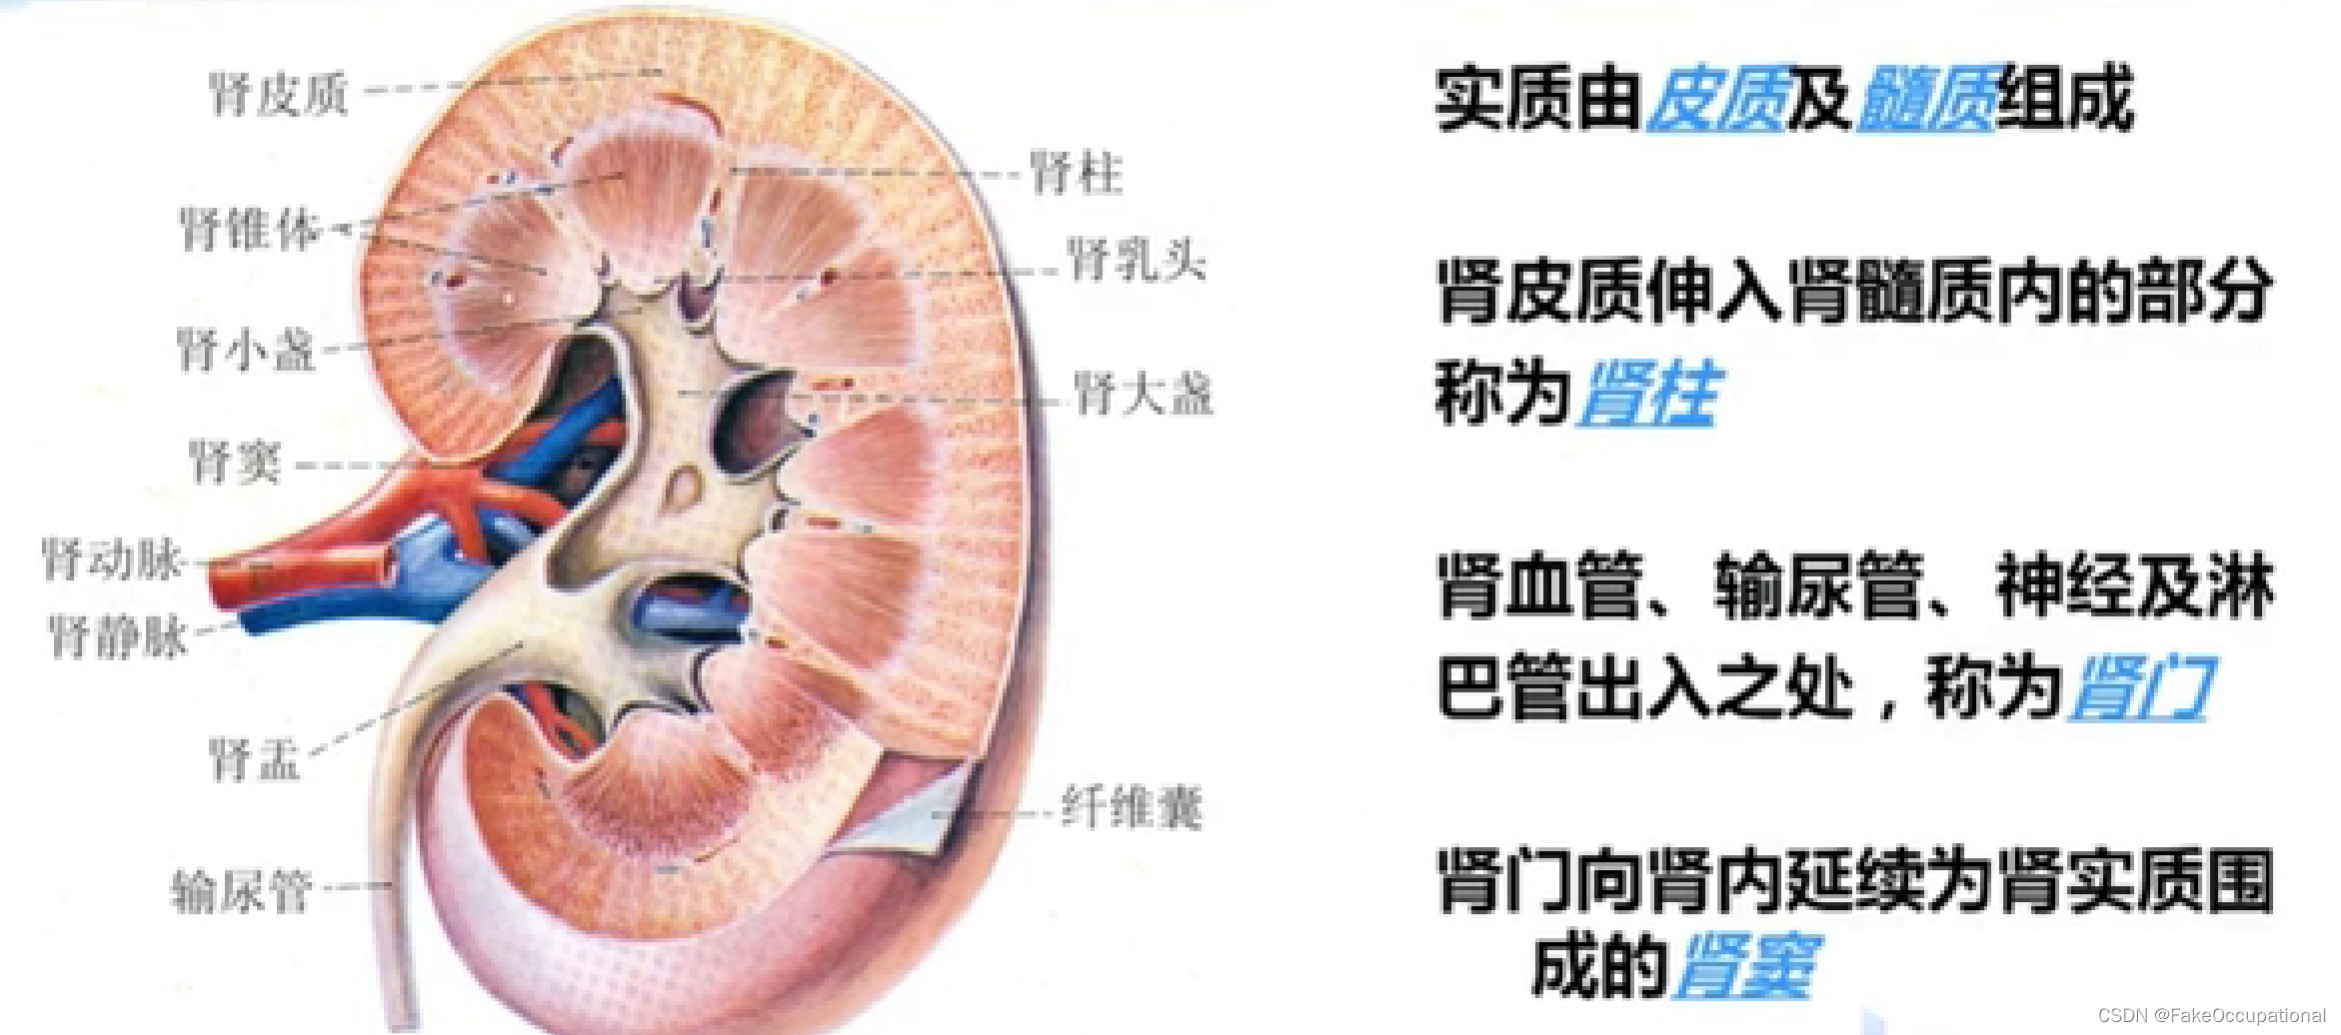

肾脏解剖概要